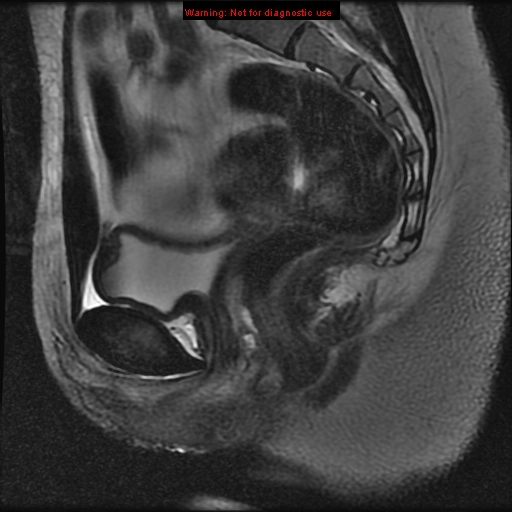

Tử cung hai sừng (Bicornuate uterus)